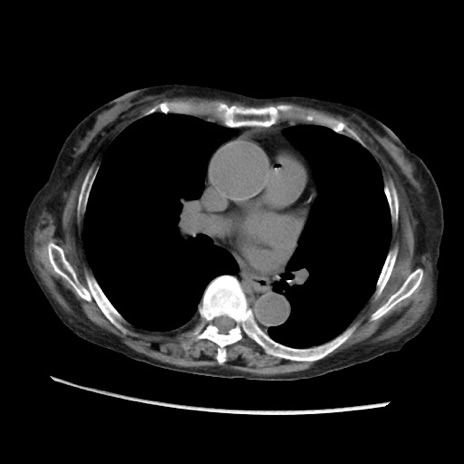

症例31(横断像)

【症例】80歳代 女性

【主訴】腹部膨満感

【現病歴】他院にて肝硬変にてフォロー中。1週間前から便秘、腹部膨満感、臍部腫瘤あり受診となる。

【既往歴】肝硬変

【身体所見】腹部膨隆あり、皮膚変化なし、疼痛なし。

【データ】WBC 4600、CRP 0.25